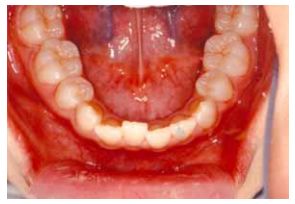

28 當上顎後牙之頰側咬頭咬在下顎後牙頰側咬頭之舌側(如圖所示)時,下列何者最能描述此種情況? (A)正常咬合 (B)頰側錯咬 (C)舌側錯咬 (D)完全錯咬